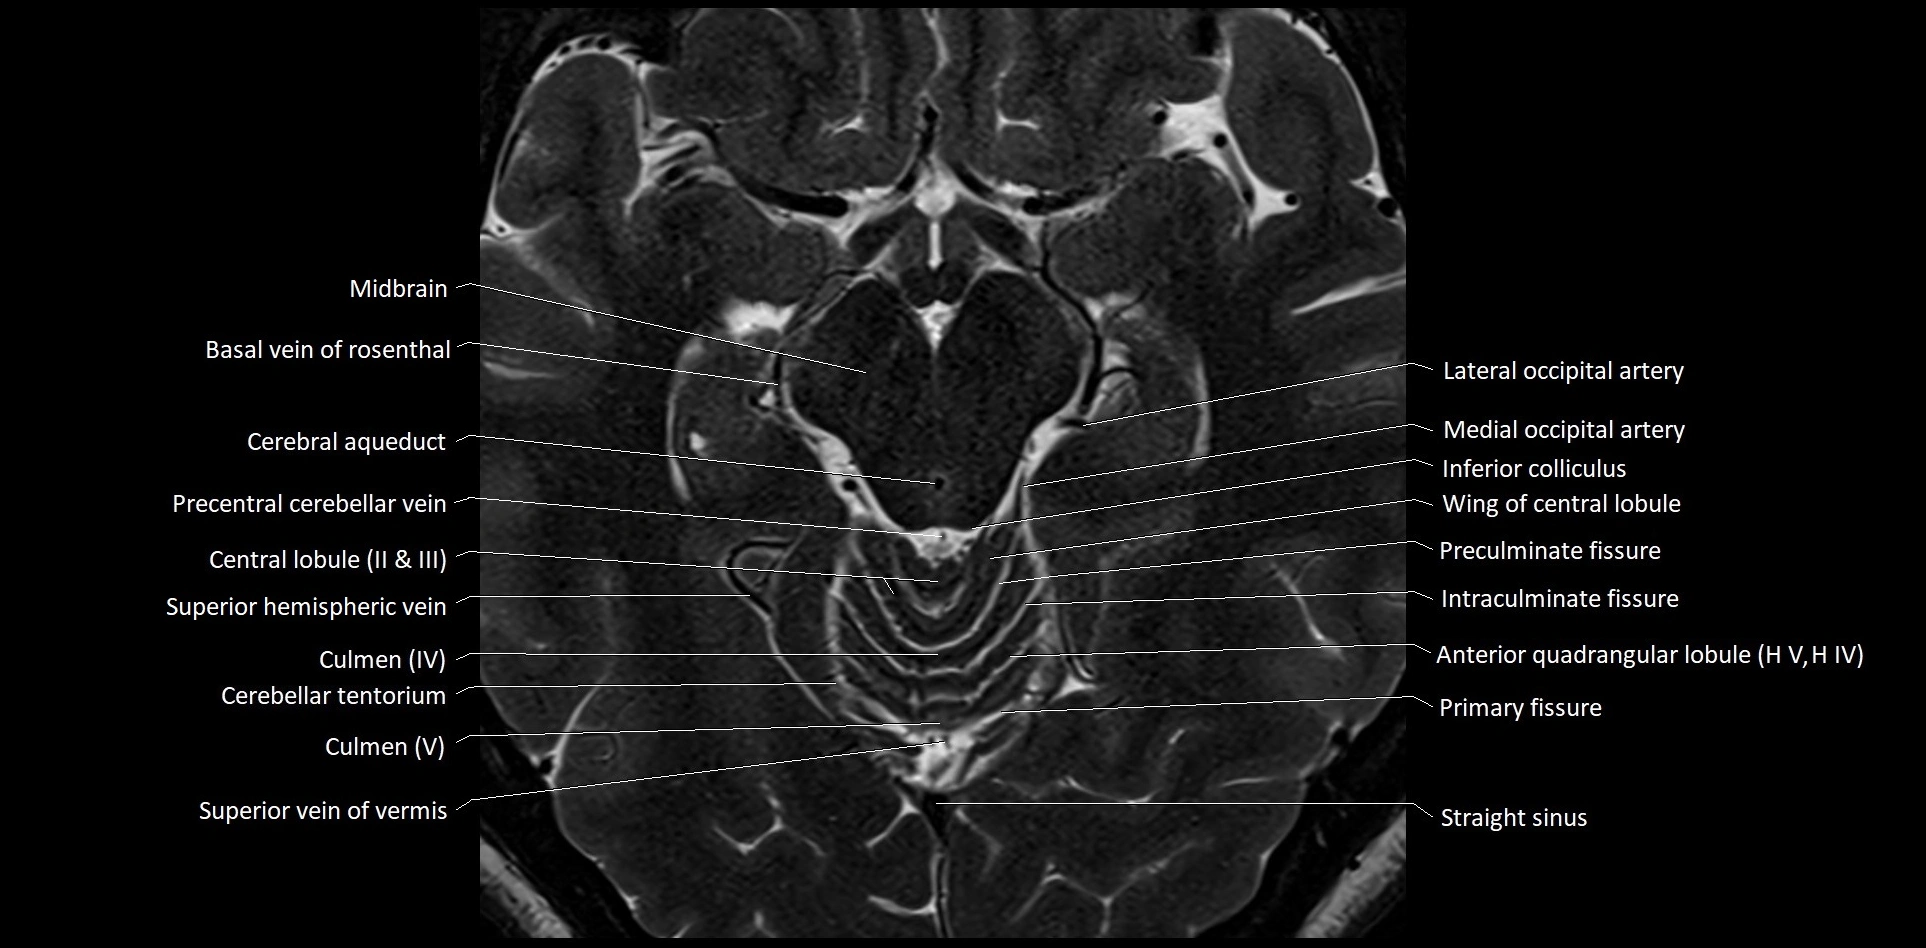

- Central lobule (II & III) of Cerebellum

- Culmen

- Culmen (IV, V) of Cerebellum

- Intraculminate fissure

- Lateral occipital artery

- Medial occipital artery

- Precentral cerebellar vein

- Preculminate fissure

- Primary fissure

- Straight sinus

- Superior hemispheric cerebellar veins

- Superior hemispheric veins of the cerebellum